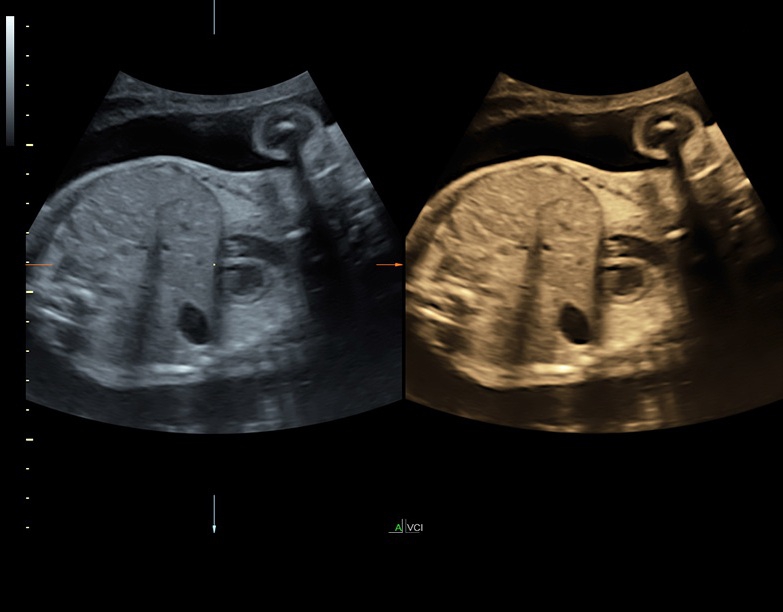

Аппарат Voluson S8 базируется на надежной платформе VCA, которая имеет множество положительных отзывов. Она обладает высококонтрастной технологией объемной реконструкции, обеспечивая качественное воспроизведение изображений. Информация выводится на широкоформатный цветной монитор размером 23 дюйма для убедительной демонстрации плода будущим родителям и облегчения работы врача.

• Высокое качество изображений: Voluson S8 обеспечивает высококачественные изображения, позволяющие детально оценить состояние плода и обнаружить возможные патологии.

• Технология автоматической фетометрии в 2D режиме (SonoBiometry): Эта технология позволяет автоматически измерять бипариетальный размер, окружность головы, окружность живота, длину бедра и плеча плода, обеспечивая точные и надежные измерения.

• Стандартизованные измерения толщины воротникового пространства и IV желудочка головного мозга плода в I триместре беременности (SonoNT и SonoIT): Эти технологии позволяют в полуавтоматическом режиме измерять толщину воротникового пространства и размеры желудочка головного мозга плода в первом триместре беременности, что помогает в ранней диагностике возможных аномалий.

• Технология SonoRenderlive: Эта технология облегчает получение 3D/4D изображений путем автоматического изменения положения плоскости визуализации в зависимости от движений плода. Она позволяет получить реалистичные и объемные изображения, что полезно для демонстрации плода будущим родителям и для дополнительного анализа.

Все эти технологии на ультразвуковом сканере Voluson S8 способствуют улучшению точности диагностики, облегчению процесса измерений и получению детальных изображений для более полного понимания состояния плода.